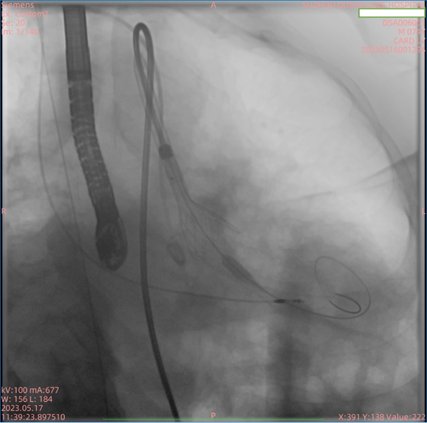

5月17日上午,在多学科协作诊疗(MDT)团队的倾力协助及全体医护人员的共同努力下,苏州市独墅湖医院(苏州大学附属独墅湖医院)心血管内科周亚峰教授团队成功地为一名“Type 0型”主动脉瓣二叶畸形合并重度狭窄患者完成了经导管主动脉瓣置换术(以下简称“TAVR”),手术顺利,术后效果显著。此次手术使用的经导管主动脉瓣膜系统,为前沿独特创新技术,不仅帮助患者解除了困扰多年的病痛,同时也体现了我院心内科在处理复杂病例方面较高的技术水平和丰富的经验,标志着我院在高难度微创心血管介入领域取得突破性进展。

患者为74岁男性,因“反复胸闷1年余,加重1周”入住我院心内科病房。入院后完善心脏彩超,根据结果诊断为主动脉瓣重度狭窄。此次手术选用园区某生物医药公司自研的瓣膜,术前跨瓣压差测得68mmHg左右,术后即刻跨瓣压差小于5mmHg,手术效果较好。